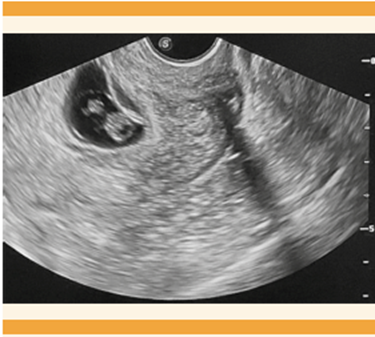

A todas las pacientes con diagnóstico de embarazo en la cicatriz de cesárea se les practicó una ecografía transvaginal al ingreso, como parte del procedimiento diagnóstico. Entre los hallazgos ecográficos (Cuadro 2) se encontró que la totalidad de pacientes se captaron en el primer trimestre del embarazo, con menos de 8 semanas de gestación. Todas las pacientes contaron con hallazgos ecográficos de un saco gestacional con características ecográficas adecuadas y aparición de estructuras embrionarias, tanto vesícula vitelina como embrión, 8 pacientes tuvieron embriocardia positiva, previa a la intervención.

La modalidad transvaginal es la óptima para la evaluación de estos embarazos, por el aporte de mayor resolución en las imágenes, donde se recomienda la evaluación en escala de grises, sumada a imágenes al Doppler color.13 Un enfoque propone los siguientes criterios ultrasonográficos para diagnosticar embarazo en la cicatriz de cesárea, en donde no necesariamente se cumplen todos: una cavidad uterina y endocérvix vacíos; placenta, saco gestacional o ambos incrustados en la cicatriz de la histerotomía; un saco gestacional triangular o redondeado u ovalado que llena el “nicho” de la cicatriz; una capa miometrial delgada o ausente entre el saco gestacional y la vejiga; un patrón vascular abundante o prominente en el área de una cicatriz de cesárea; y un polo embrionario o fetal, saco vitelino, o ambos con o sin actividad cardiaca fetal.4